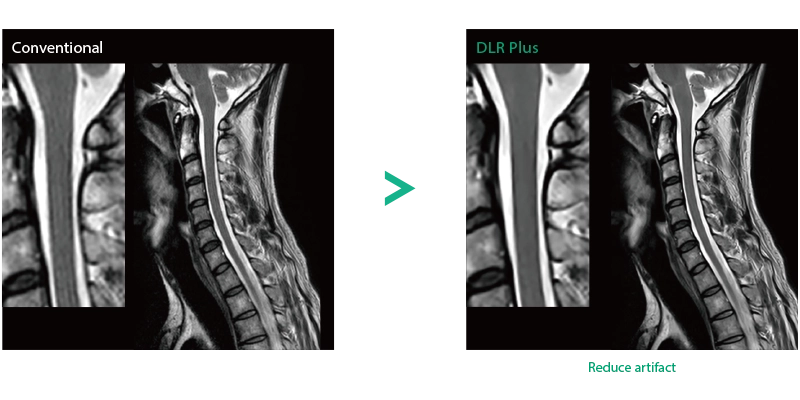

"DLR" is applicable to all body parts and promotes high speed imaging and diagnostic efficiency

IP-RAPID x DLR Plus can also shorten imaging time, allowing more images to be taken in the same examination time.

Deep Learning technology*8 enables image quality adjustment after imaging is complete. It optimize SNR and improve image sharpness by processing MRI signals in stages (k-space signal processing). This brings super-resolution and reduces truncation artifacts.